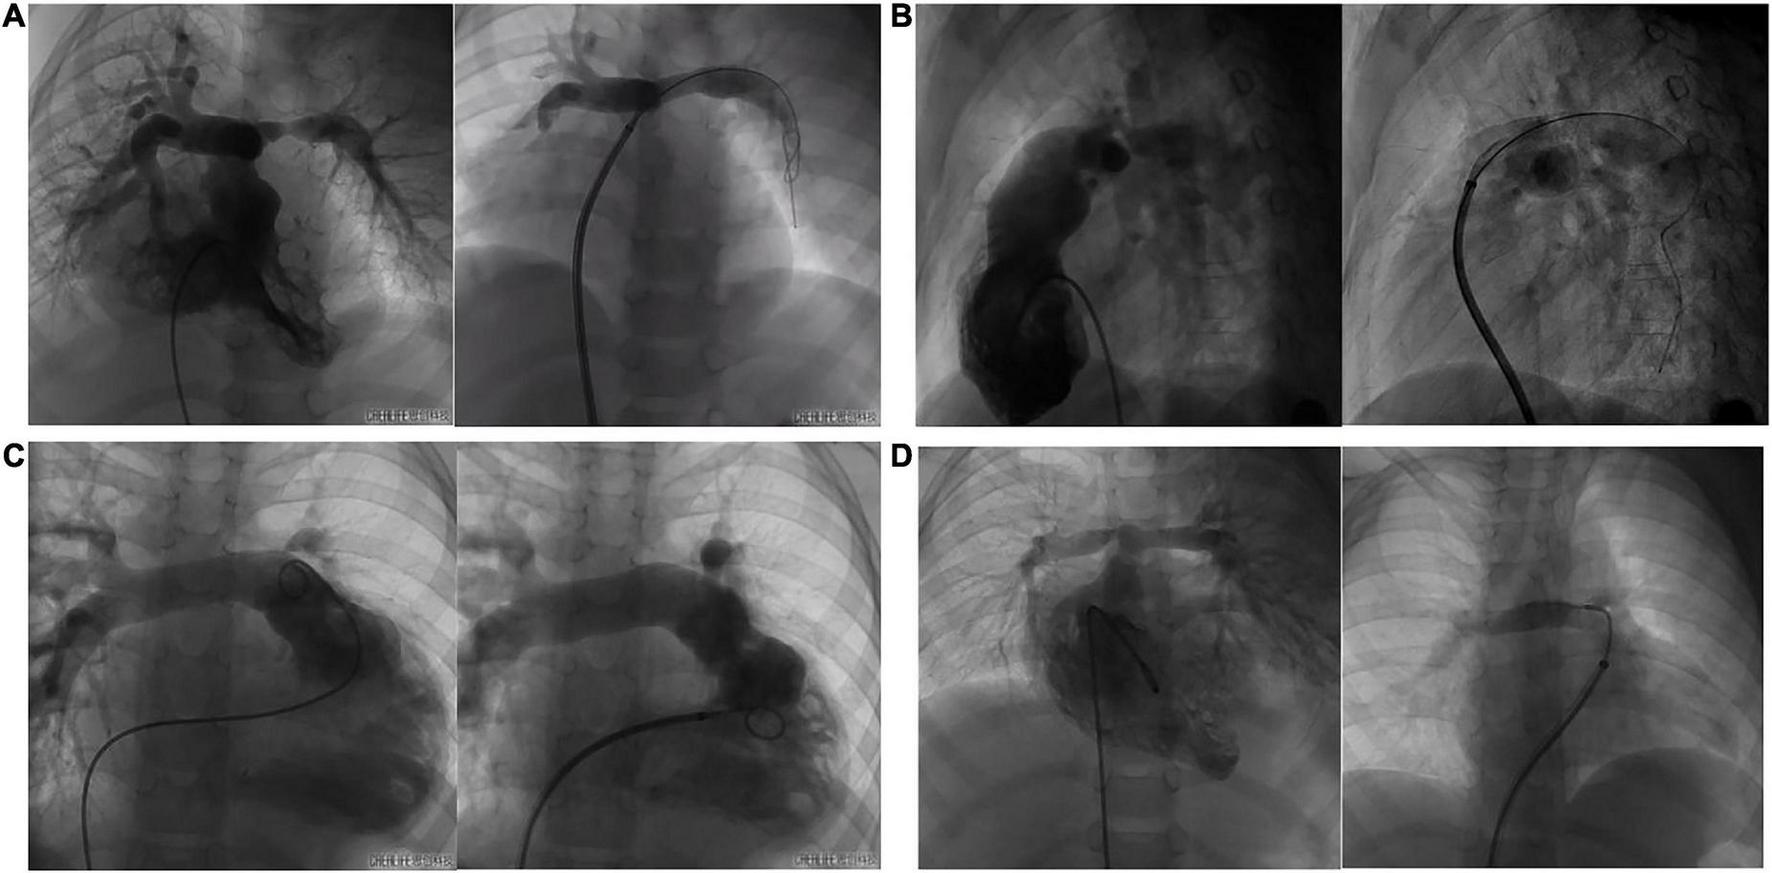

Eleven cases underwent right heart catheterization under general anesthesia. The measured parameters included: A1 (narrowest diameter), L (length of the lesion vessels) and A2 (distal normal diameter of the lesion vessels). The hemodynamic parameters included: preoperative/postoperative right ventricle (RV) pressure, main pulmonary artery (mPA) pressure, and pressure gradient (Table 3). Nine patients had stenting in the left pulmonary artery, and three had stenting in the right pulmonary artery. The DSA images before and after pulmonary artery stenting are shown in Figure 5. The diameters of the stents were 10 mm in three patients, 8 mm in six patients, 6 mm in two patients, and 5 mm in one patient. The lengths of the stents were 23 mm in nine patients, 28 mm in two patients, and 18 mm in one patient. The sizes of the delivery sheath used ranged from 6 to 8F and the balloon pressures ranged from 12 to 16 atm.

FIGURE 5

The DSA images of before and after pulmonary artery stenting. (A): case 1 had PA/VSD, LPS and implanted IBS; (B): case 8 had TOF, LPS and implanted IBS; (C): case 3 had VSD, LPS and implanted IBS; (D): case 5 had TGA, RPS and implanted IBS.